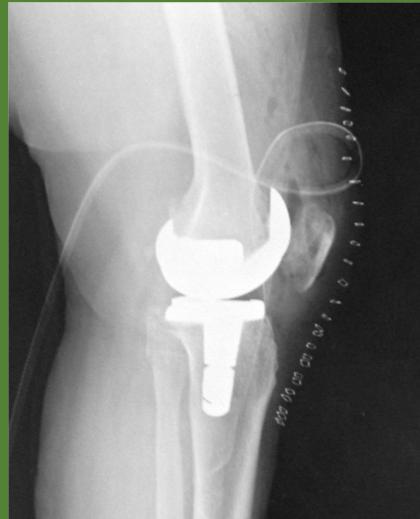

Surgical Considerations

- Timing: When conservative measures fail

- Options:

- Arthroscopy (selective cases)

- Osteotomy (young patients with unicompartmental disease)

- Total knee arthroplasty (end-stage disease)